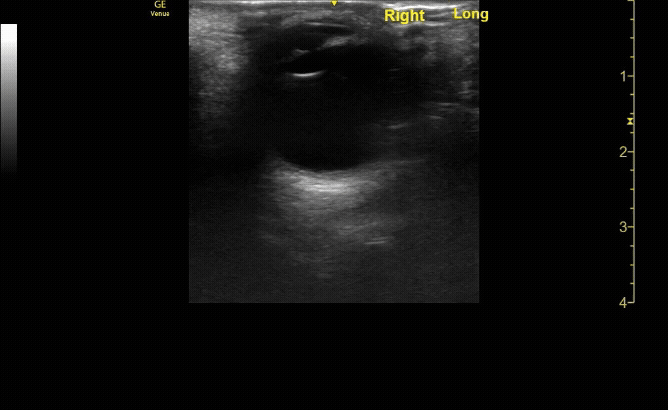

Sagittal (long) view of the right eye. Ensure to scan both right and left for credit.

c/o Victoria Gonzalez